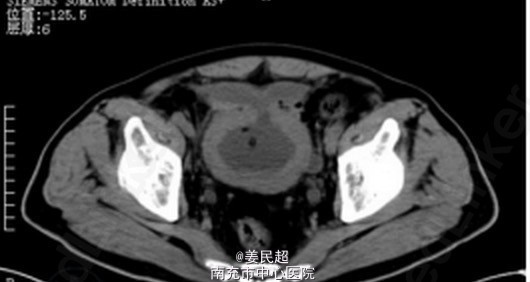

因患者一般情况良好,各项生命体征平稳,无明显腹胀、腹肌紧张,故降低冲洗速度,继续修整切除前列腺尖部增生腺体。术后留置导尿、缓慢膀胱冲洗。术后CT检查显示膀胱前壁有一破裂口,位于腹膜外(图2)。患者恢复良好,10d后拔除导尿管,自行排尿通畅。 气体爆炸与爆炸性气体在膀胱内聚集有关。电切过程中由于高温电灼、组织碳化,组织受热分解产生以氢气为主的混合性气体。膀胱内气体爆炸可以无明显膀胱损伤,也可出现膀胱黏膜撕裂、腹膜外或腹膜内膀胱破裂甚至合并肠管损伤等严重并发症。术中闻及气体爆炸声后,必须立即停止操作,仔细检查膀胱损伤情况。膀胱损伤轻微或虽有腹膜外膀胱破裂但破裂口较小时,可根据患者当时情况决定是否继续手术,术后保持膀胱空虚状态使其愈合。若破裂口较大、多处破裂、伴有活动性出血或腹膜内膀胱破裂时,需立即改开放性手术进行膀胱修补等处理。